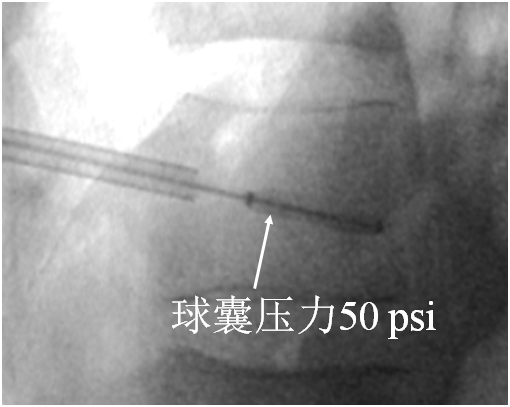

术中球囊压力指征

• 球囊压力直接来源于周围松质骨和软组织:        预扩张:50~70psi,可拔出内芯。        扩张松质骨:70~300psi。        球囊最终压力不超过300psi。

• 球囊扩张,挤压周围松质骨产生空间时压力明显增加。

• 骨折复位后,压力逐渐下降,延长球囊扩张时间。